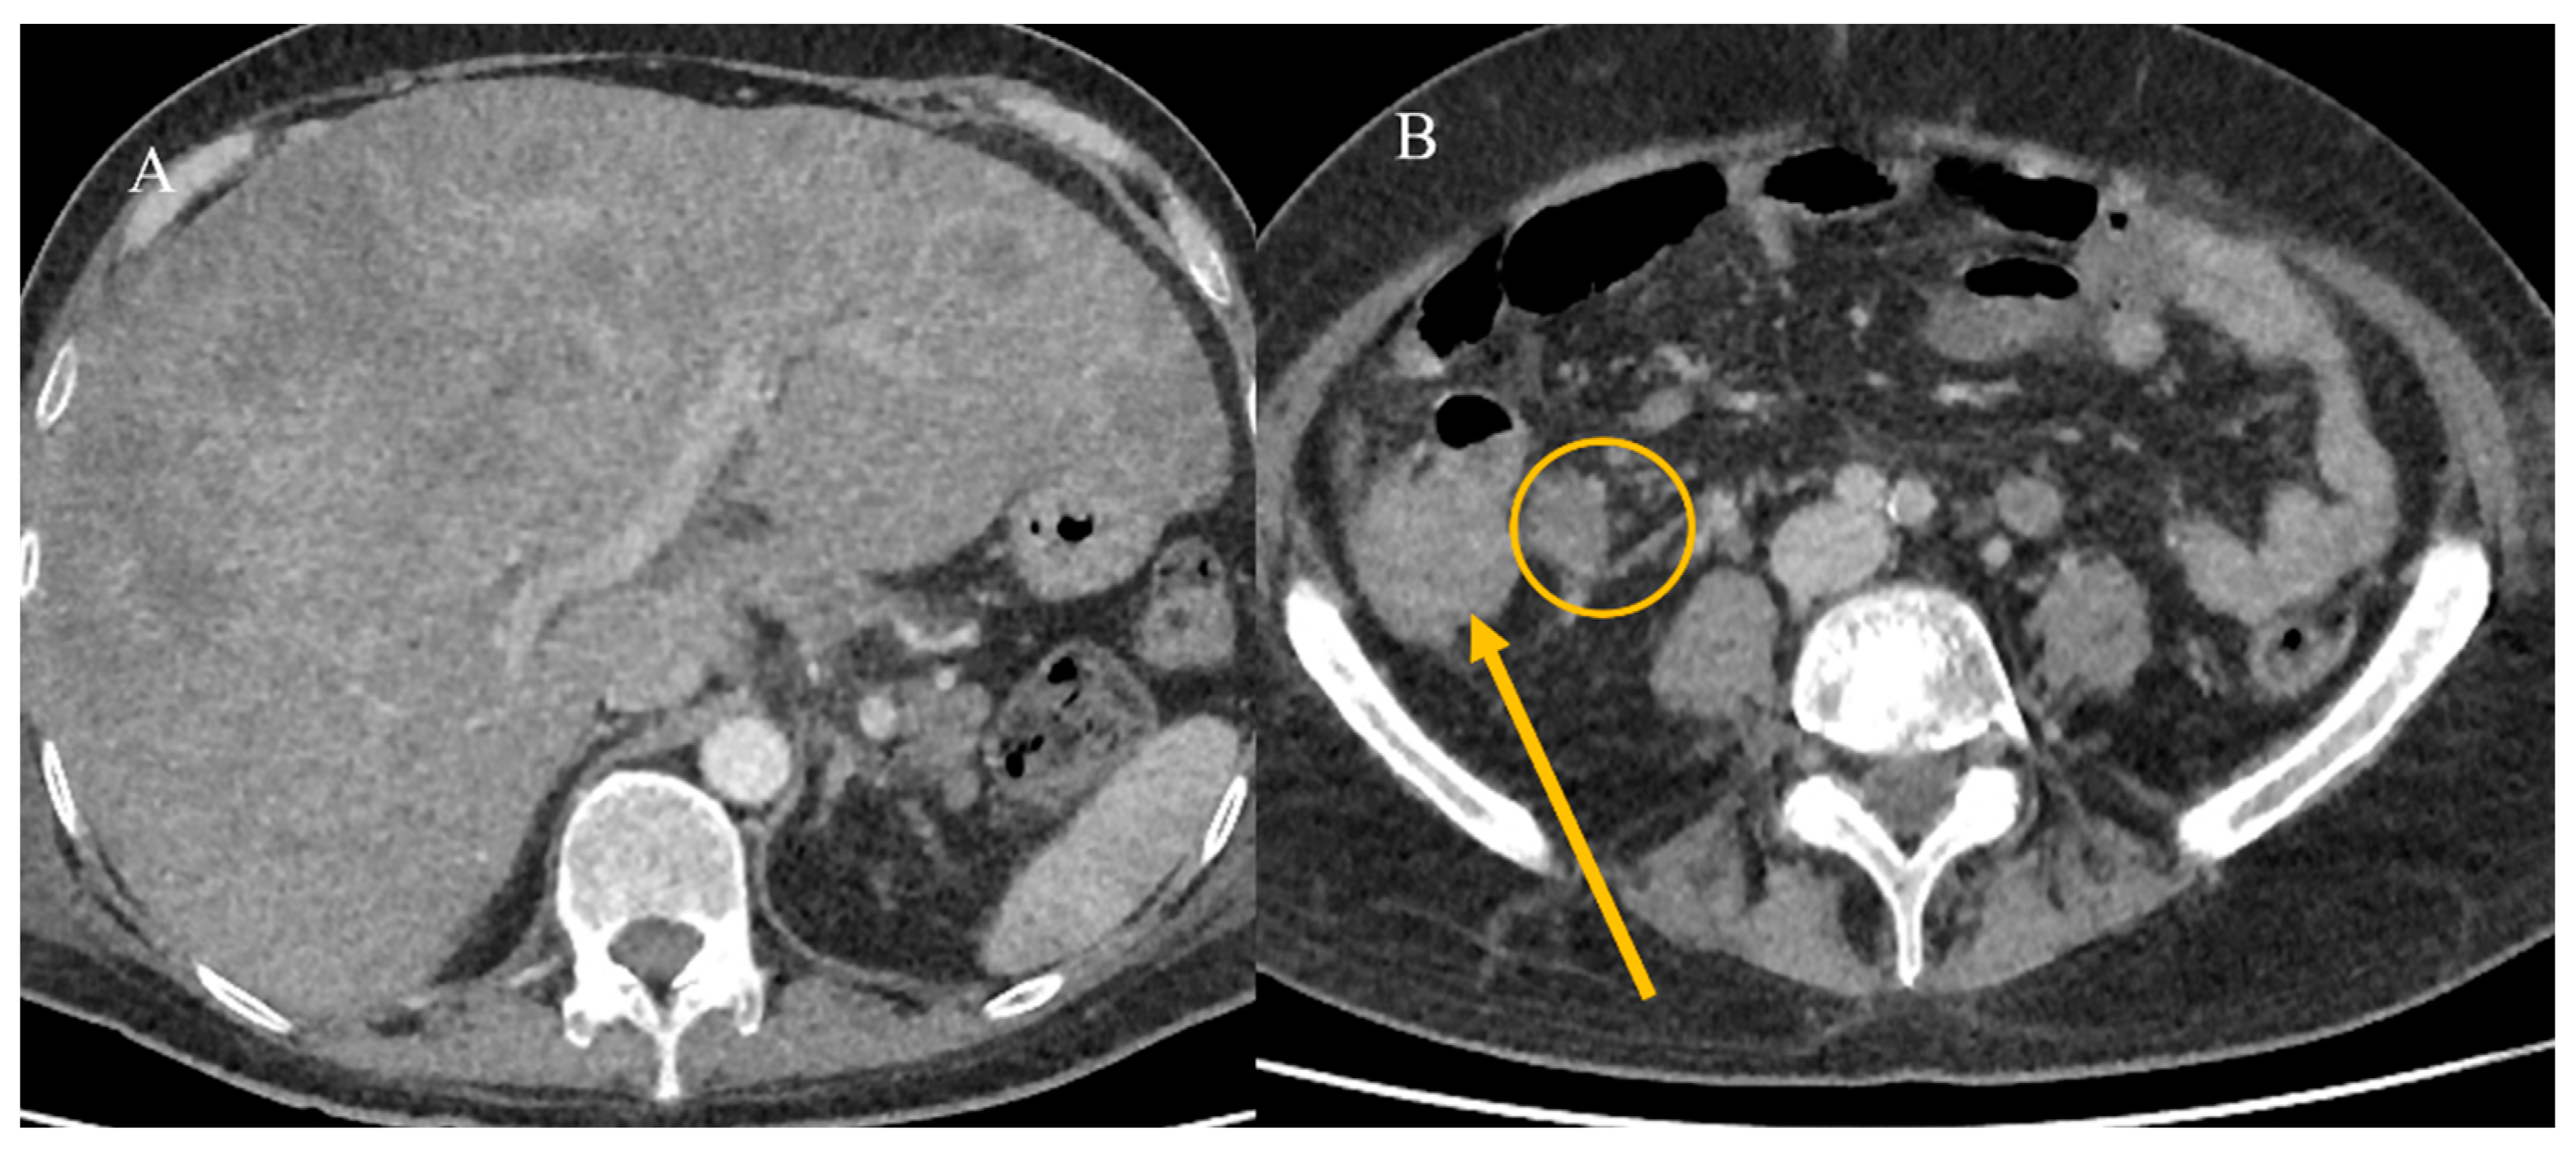

2.5. Small Bowel Tumors Presenting with Bleeding, Ischemia, and Perforation

2.7. Metastatic Presentation of Small Bowel Tumors